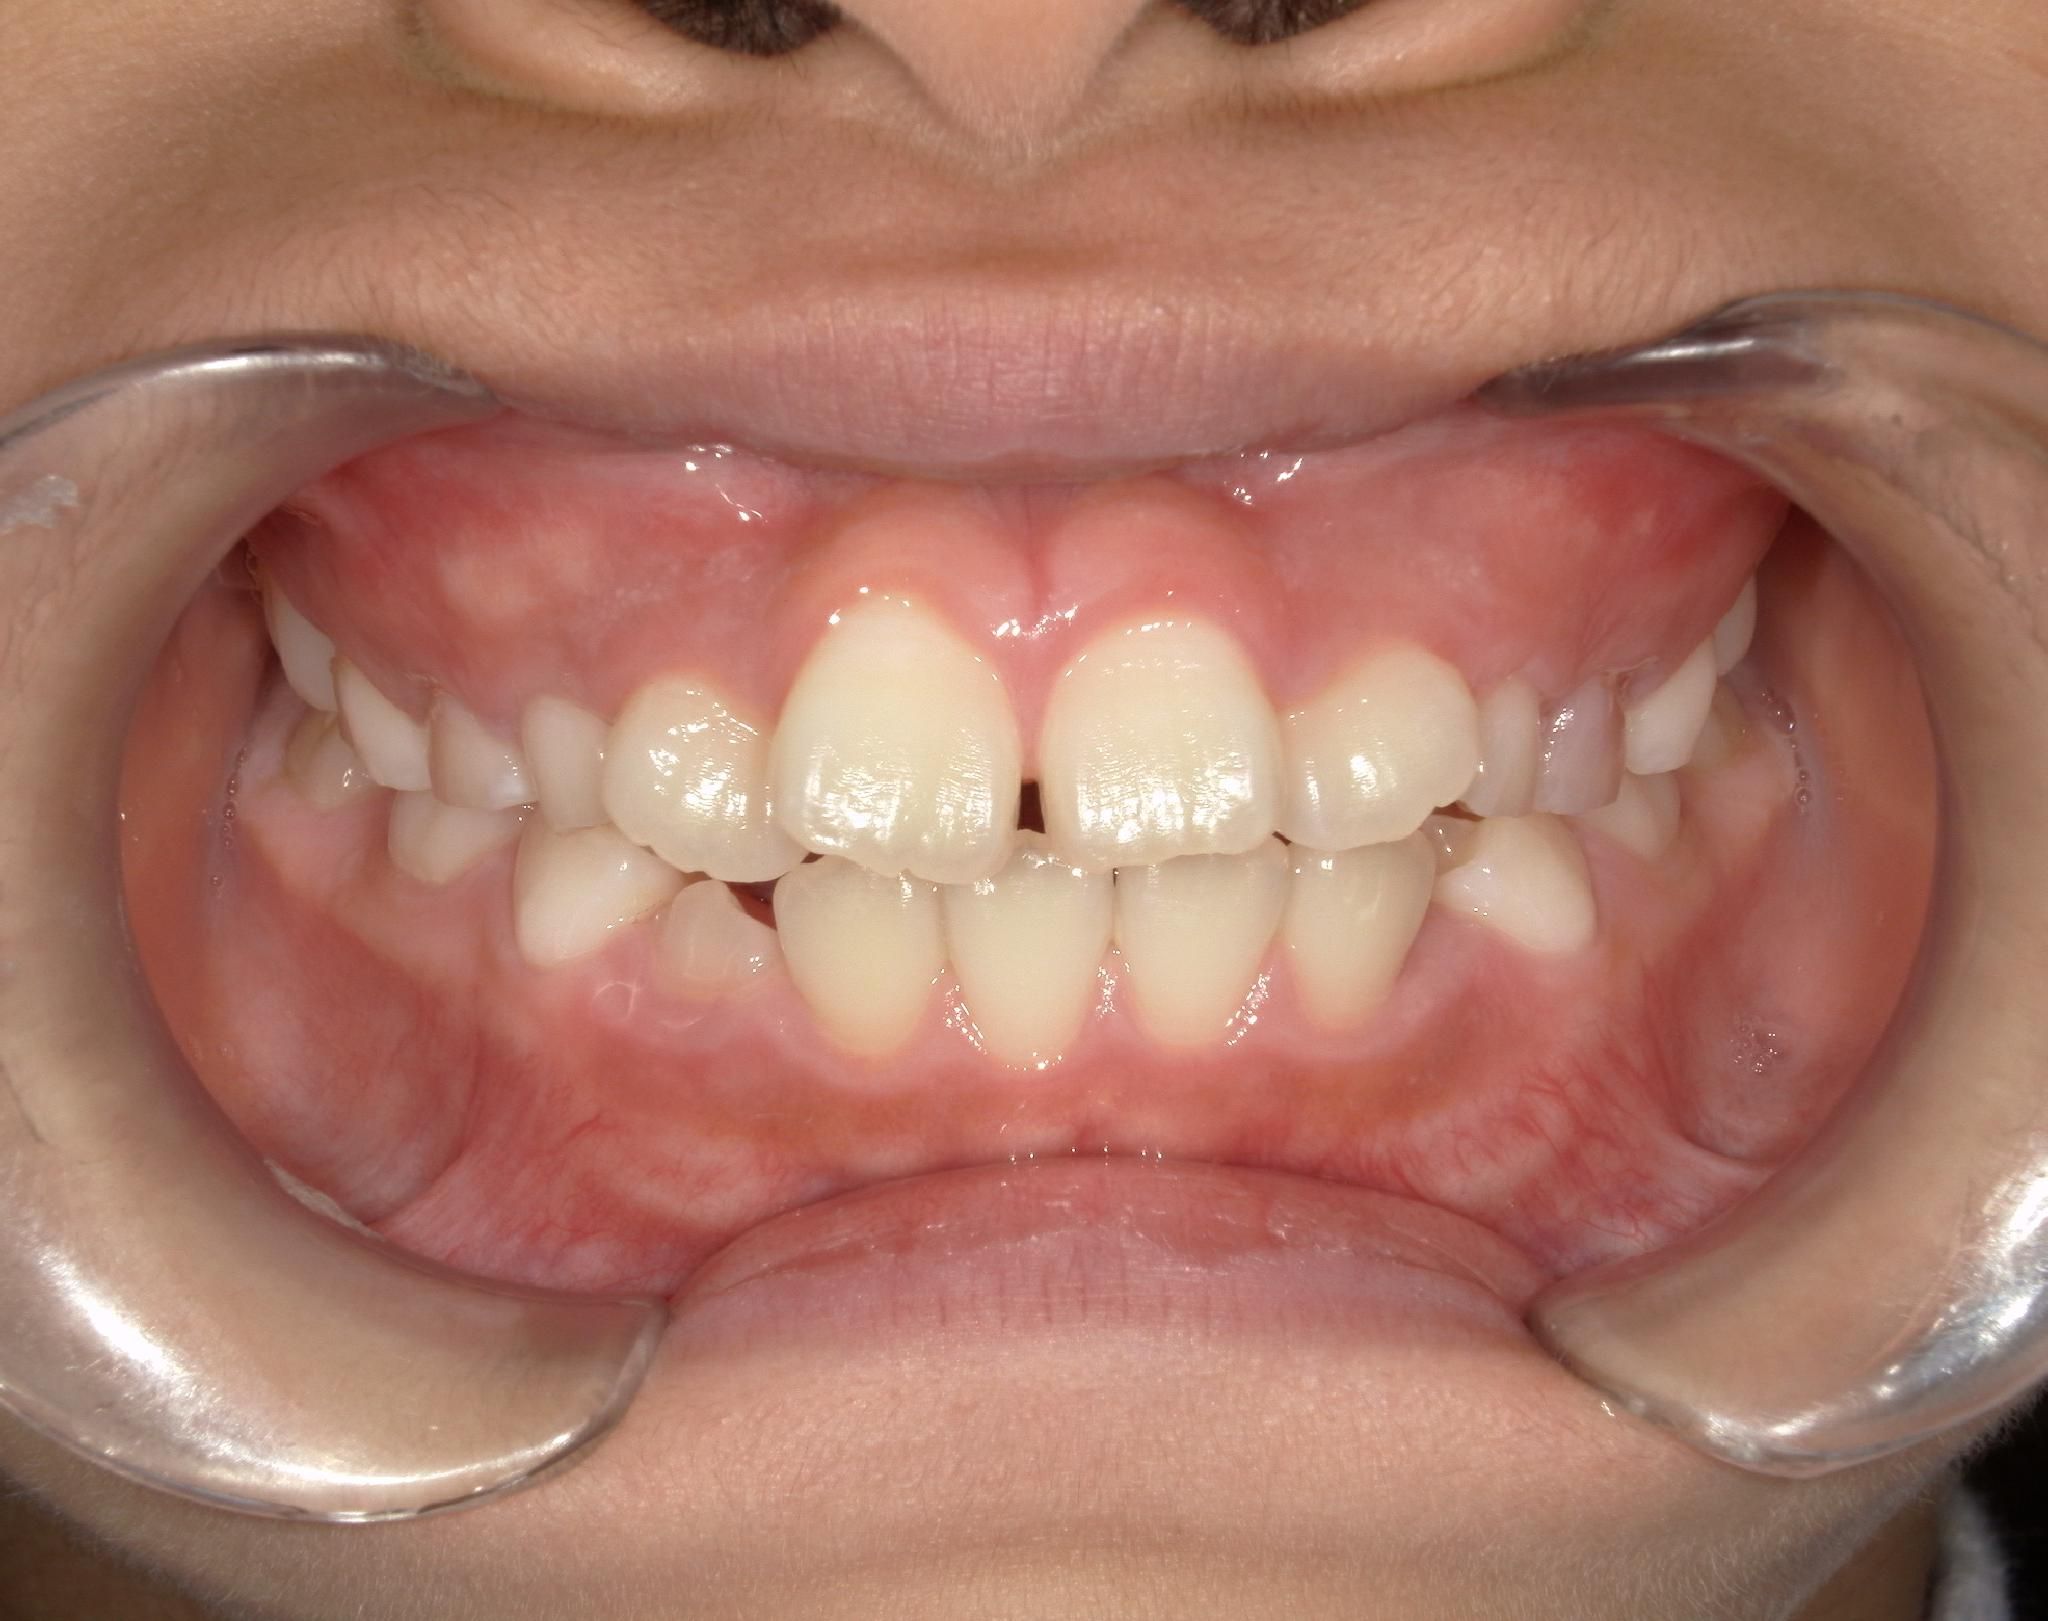

治療後After

ガタつきもなく、きれいなアーチになりました